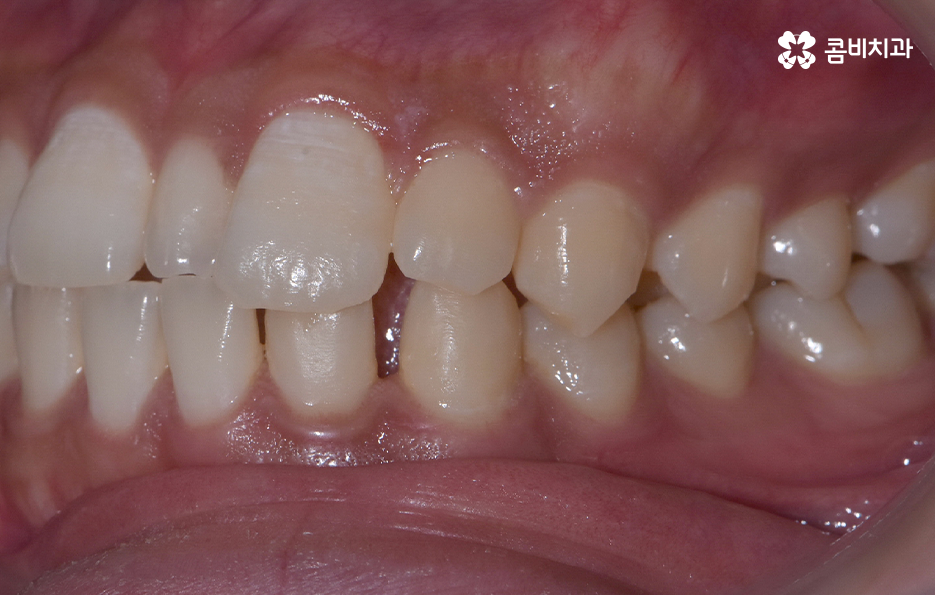

과잉치 중에서는 어떤 치아가 과잉치인지 구분이 어려울 정도로 일반적인 정상 치아의 크기와 비슷한 크기와 형태를 띄는 경우도 있는 반면에 위 사진의 케이스는 첫번째 앞니와 앞니 사이에 유독 작은 왜소치가 있는 형태이기 때문에 치아의 기능적인 문제 보다는 심미적인 개선을 필요했던 케이스로 볼 수 있어요

그나마 다행인 점은 앞니만교정을 하더라도 치아의 교합이나 골격적인 부분, 얼굴형 등에 있어서 큰 지장은 없던 경우였는데요. 물론 아랫니가 다소 벌어져 있기 때문에 전체교정을 하면 더 좋은 결과를 얻을 수 있었겠지만 환자분의 니즈에 있어서 앞니만교정을 빠르게 원했던 사례이기 때문에 앞니 부분의 과잉치 발치 후 앞니만교정을 부분적으로 진행했어요

과잉치로 인해서 치아 배열이 전체적으로 불규칙해지는 경우도 있고 돌출입의 형태로 나타는 경우도 있지만 다행이도 입술라인이나 얼굴형에 있어서 돌출은 크지 않은 상태였다는 점도 앞니만교정을 해도 어느정도 좋은 결과를 낼 수 있던 케이스로 볼 수 있어요

과잉치로 인해 말그대로 치아의 정상 범위 이상으로 치아가 배열되기 때문에 다른 치아의 배열에도 악영향을 주는 경우가 많지만 위 환자분의 케이스의 경우에는 치열 자체는 전체적으로 가지런한 편이라는 점과 특히 턱뼈가 넓은 편이라는 점에서 전체교정을 하지 않았어도 환자분이 원하는 치료의 목표는 달성할 수 있었어요